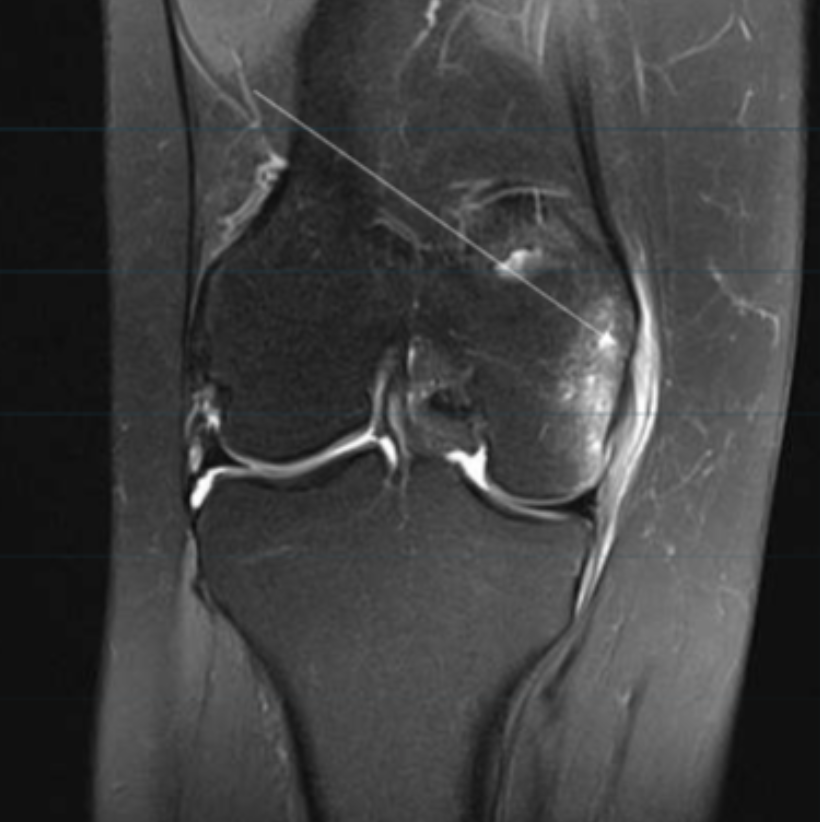

Describe the pathology indicated by the arrow (Cor PD FS).

MCL tear